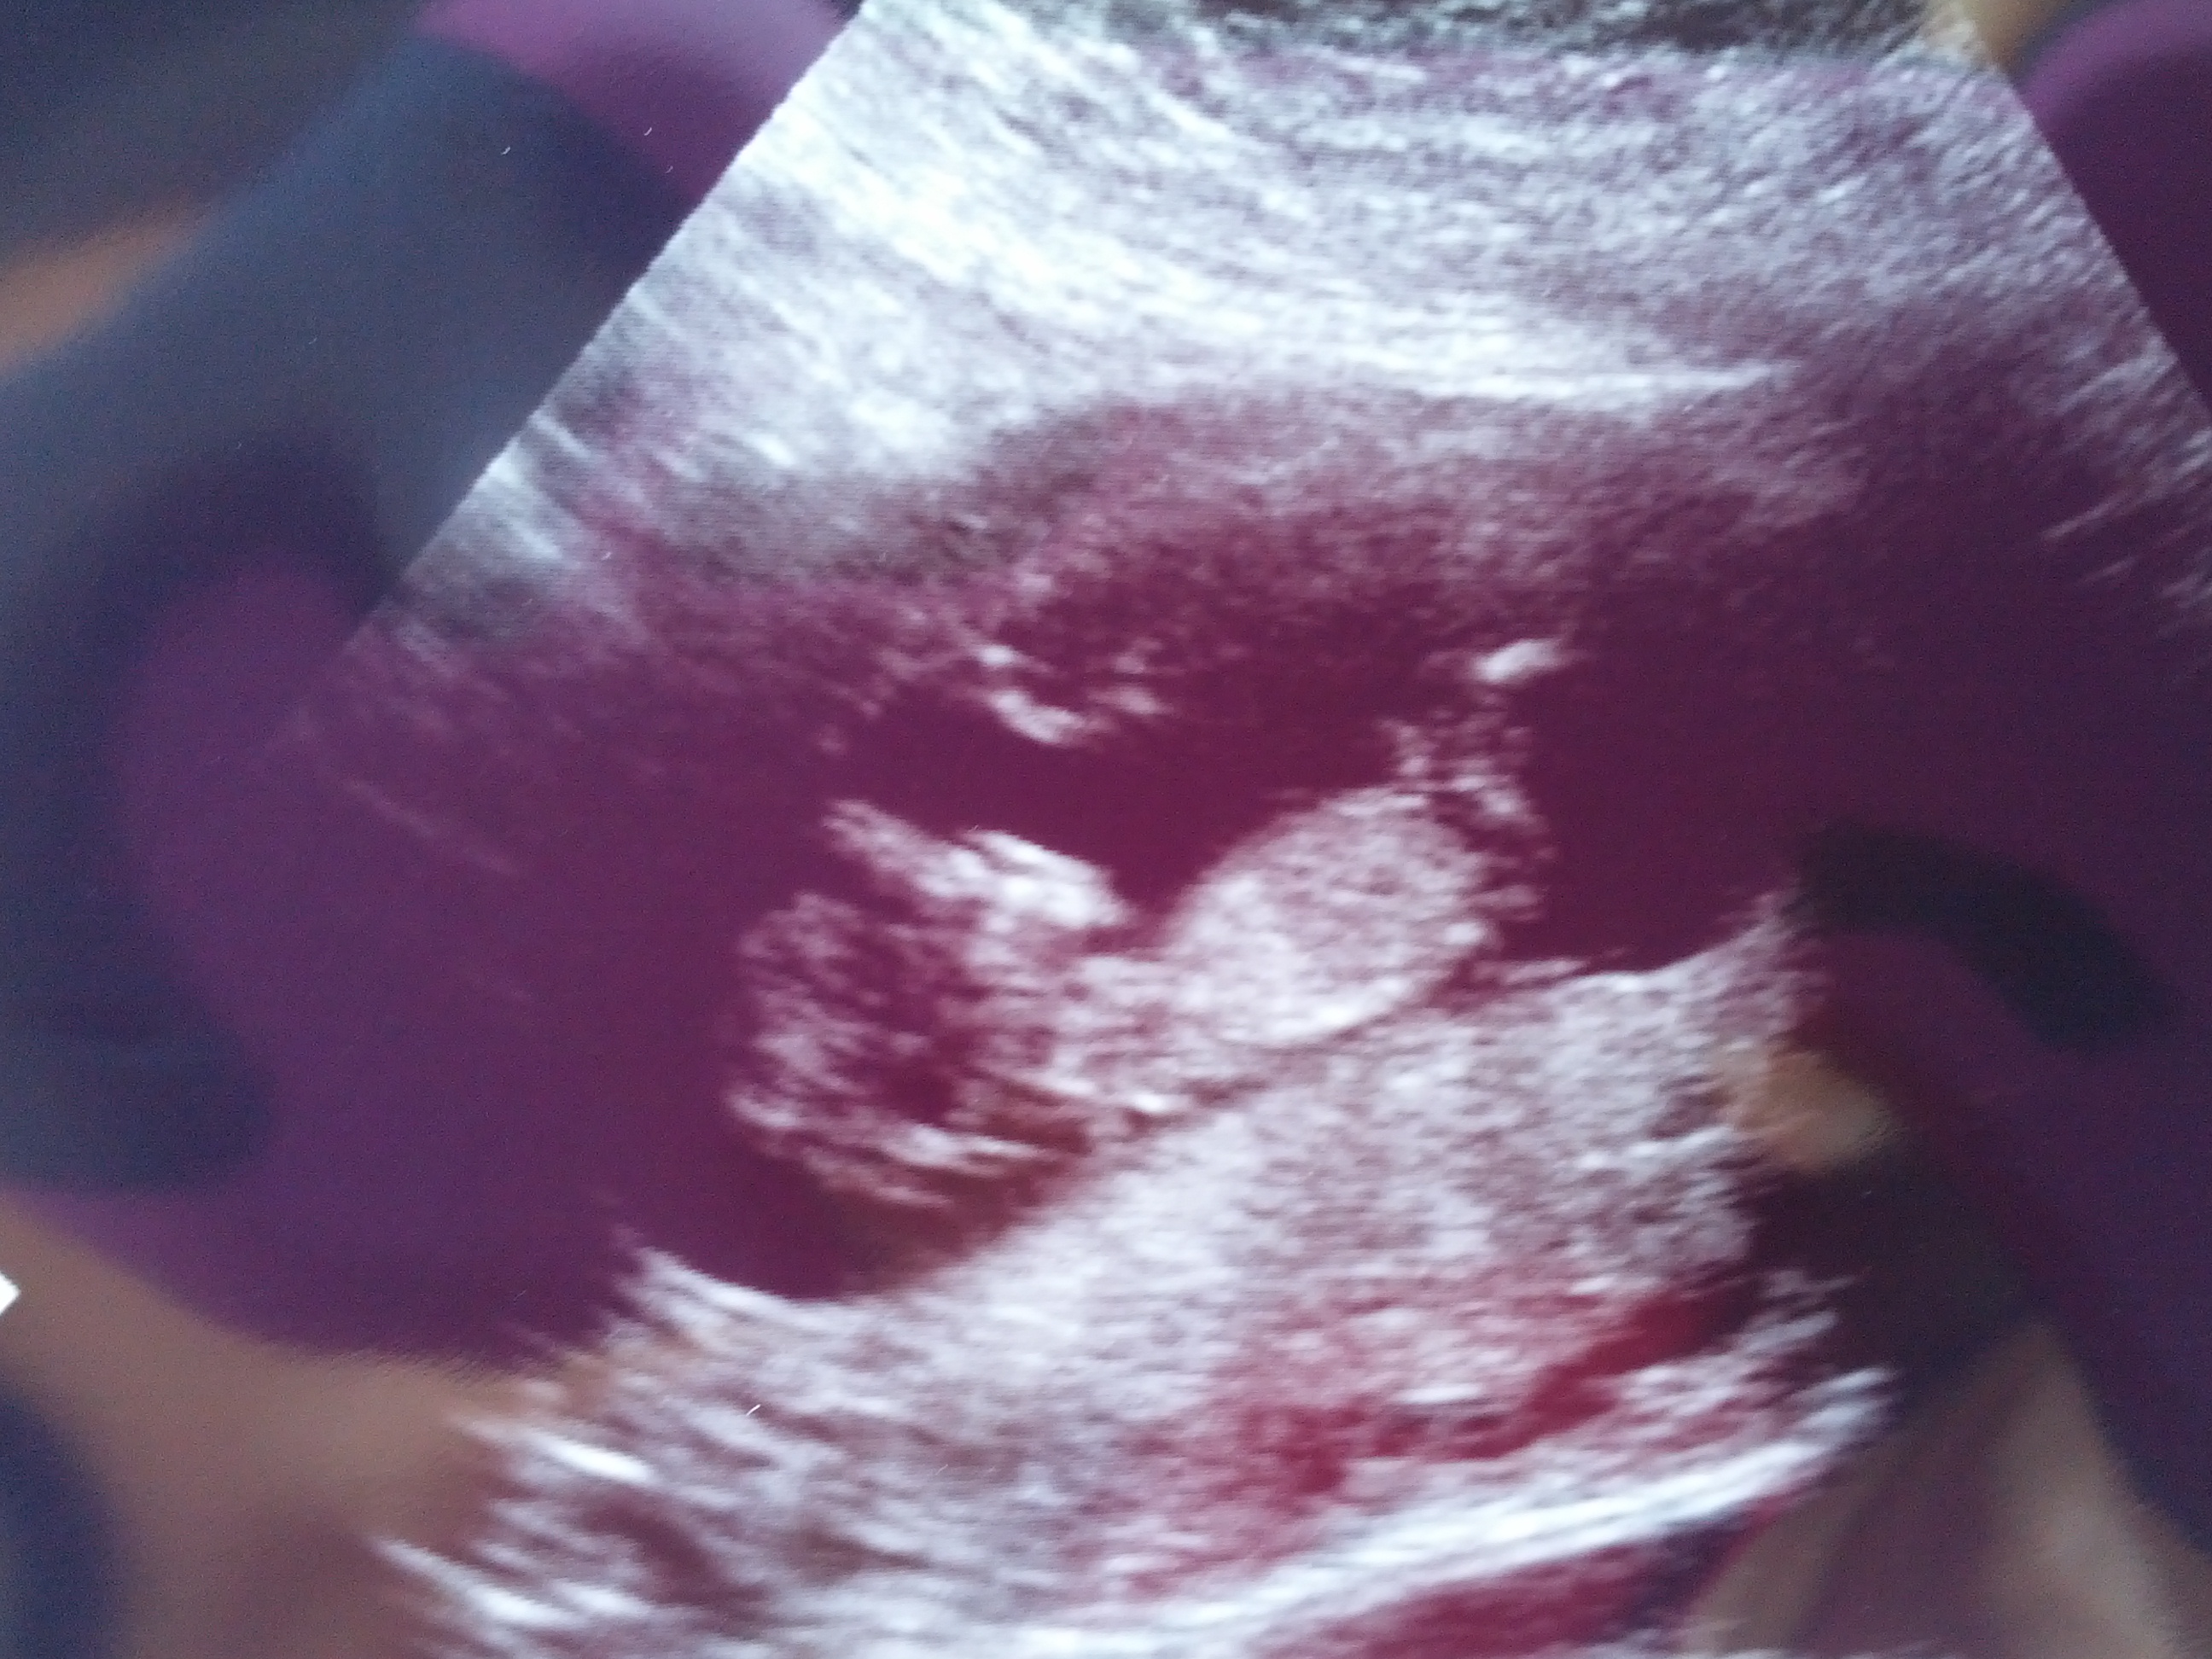

The tech told me the baby was not in profile view...but I've had a couple people tell me they think it is in profile. The nub is very visible, but I"m not sure if it's a reliable position to guess from? Please give me your honest opinions of what direction the baby is facing and whether a nub guess is possible...Thank you!!!

I'm going to add another pic taken at the same time, but was abdominal instead of transvaginal, so it's not as clear...would love more opinions on these pics! (putting the origianl photo from this post below new one so no one has to go to the first post to find it. Thanks so much!

On this 2nd one, though believe baby isn't in profile, I'm really hoping that shadow on the nub area could mean boy. What do you think?